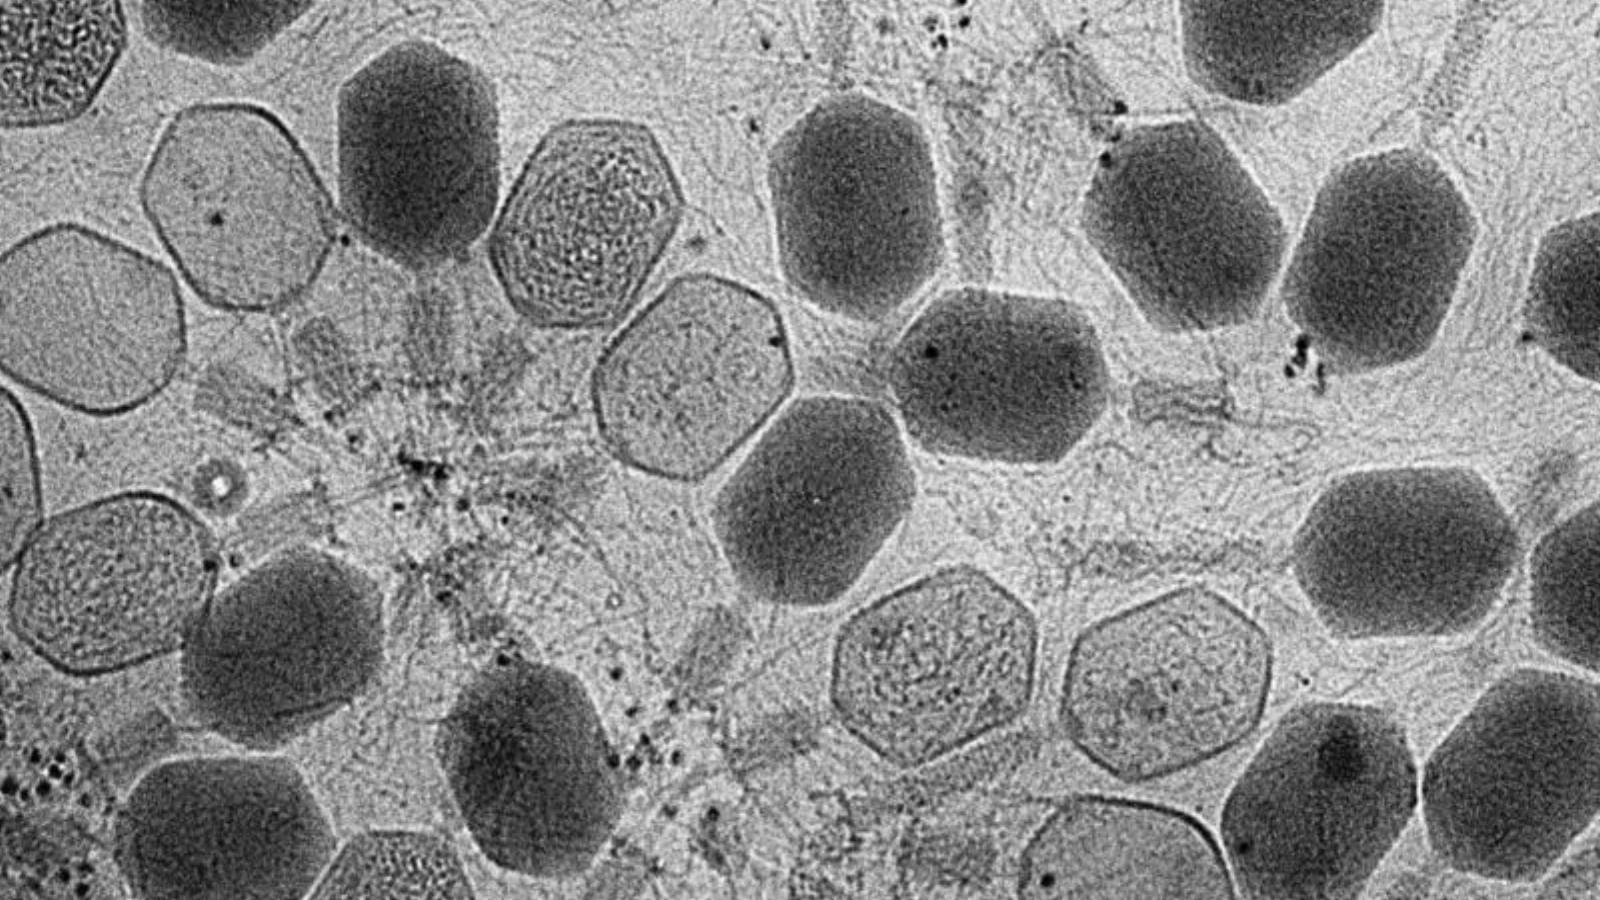

O echipă de cercetători din Australia a descoperit sute de virusuri necunoscute anterior, care trăiesc în interiorul bacteriilor din intestinul uman, transmite agenţia Xinhua.

Aceste virusuri - bacteriofagi - ar putea fi utilizate în viitor pentru remodelarea microflorei intestinale, putând influenţa sănătatea intestinală şi evoluţia diverselor stări patologice, conform unui comunicat emis joi de Universitatea Monash din Australia.

Studiul, publicat în jurnalul ştiinţific Nature, este primul de acest gen şi utilizează o abordare la scară largă, bazată pe culturi, pentru a izola şi studia bacteriofagii temperaţi din intestinul uman, se precizează în comunicat.